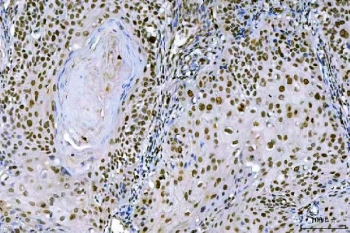

IHC staining of FFPE human laryngeal squamous cell carcinoma tissue with Ki-67 antibody. HIER: boil tissue sections in pH8 EDTA for 20 min and allow to cool before testing.